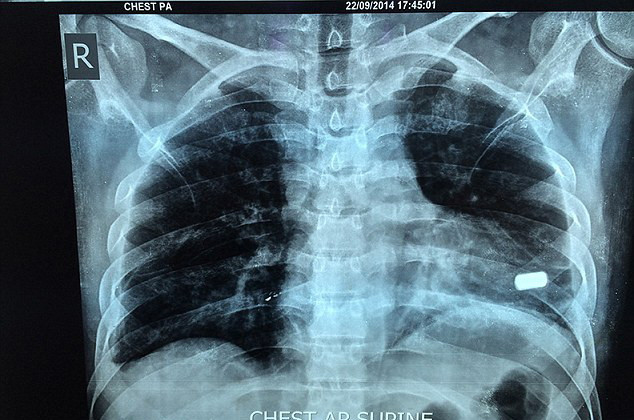

Talharii au tras doua focuri de arma si ambele gloante, de calibru 20, l-au nimerit pe Bharat Sharma, unul din ele strapungandu-i inima. La o saptamana dupa jaf, chirurgii de la Spitalul Universitar Jawaharlal Nehru din Aligarh i-au scos cel de-al doilea glont, care i-a nimerit talia.

Barbatul a trait 2 luni cu glontul in inima pentru ca medicii de la acest spital au apreciat ca viata i-ar fi pusa in pericol daca ar incerca sa-l scoata. Insa chirurgii de la un alt spital, Sal din Ahmedabad, au acceptat provocarea si i-au scos glontul miercuri.

Dr. Anil Jain, cel care a condus echipa de chirurgi, a spus: "Este un caz foarte rar... Glontul era blocat in muschiul inimii inaintea varfului ventriculului stang. A fost la un milimetru distanta de a patrunde in camera inimii. Glontul ar fi putut sa fie impins de pulsatiile inimii. Este, clar, un caz deosebit, cu o poveste unica si un barbat foarte norocos."